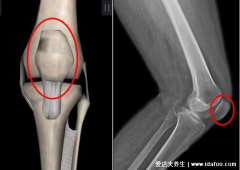

在上面已提及关节滑液对于关节健康的重要性,那在这里便稍稍介绍一下关节软骨,它就相当于关节的保护垫,能够缓冲作用到关节上的震动和冲击,并减少骨关节之间的硬性摩擦,从而起到保护关节的作用。

√ 修复受损的关节软骨:氨糖能够刺激软骨细胞的生长,促进受损软骨的自我修复,保护关节软骨。

√ 补充关节滑液:氨糖还能够促进关节滑液的分泌,润滑关节软骨面,减少骨关节之间的磨损。